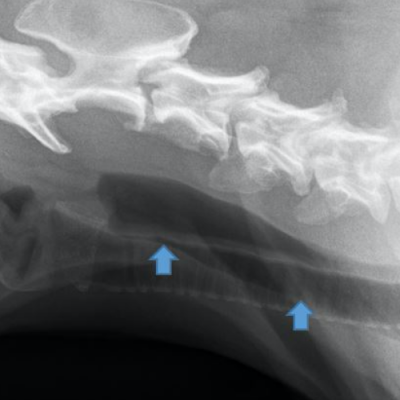

Following the outbreak of megaesophagus / polyneuropathy in Latvian dogs, a seminar will be held in Riga on 20 September to discuss the investigation into this disease,...